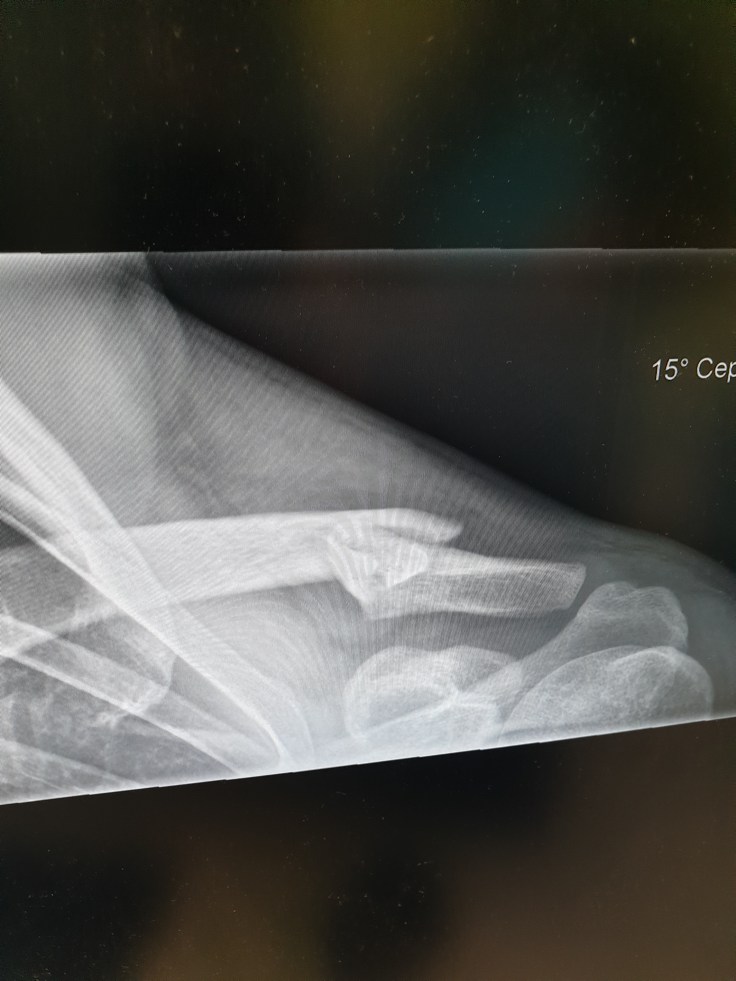

Collarbone on day 1

Collarbone after 9 days

In the days that followed, I just sat in front of the TV watching the Olympics drugged up on codeine. Sleeping, which I was worried about, wasn’t actually too bad although I had to prop myself up with pillows. For the first 4 days though I didn’t take my arm out of the sling, however after this amount of time I needed a shower. Showering wasn’t too bad either I just had my arm down by my side. That first week was the worst and having to do pretty much everything for myself still was more difficult although friends were also really helpful. After 9 days I was back at the hospital for a follow up with the fracture clinic. The X-ray although looking worse to my eyes than the day I broke the bone was healing really well according to the Dr and she discharged me for physio. I started physio in just under 3 weeks. It’s now been 10 weeks since and I’m 95% back to normal. To be honest, after about 3 weeks I was back to normal with everyday things and living, I just couldn’t raise my left arm above 90 degrees. But I had it out the sling by this point and after the 6-week point, it really was completely normal except for a few little things I’ve been a bit cautious with. Just last week (8-week mark) I started overhead pressing and push-ups again all now pain-free too. I’m pretty much fully recovered. I think it would be possible to go back up the slopes but I don’t want to do something and then ruin my 2 month road trip around NZ. There is always going to be another winter season and chance to board, but who knows when I’ll have such an opportunity to travel NZ and I don’t want to ruin that. It certainly wasn’t the season I hoped it would be. But I still have no regrets or hard feelings. I got a good feel for boarding and my first experience of a ski resort. I know I’d love to do it again and to continue on the snowsports journey. I’m no longer a beginner and would class myself as an early-stage intermediate. And while it is frustrating not knowing when I’ll be back on the board, I genuinely don’t feel bad about what happened and know I’ll be back one day. Things could have been far worse, a broken collarbone isn’t the worst injury and I’ve been able to do lots of other things which maybe I wouldn’t have had the time had I been up the mountains more. Life is full of adversity and setbacks, it’s how you handle these and move forward which determines your happiness and growth in life. A book I once read said there is a moment between a stimulus and response. In that moment you can control how you respond. How you decide to respond can determine if you wish to continue to be happy or descend into sadness and resentment about a situation. I always try to choose to be happy and grateful, to see the positives in life regardless of the stimulus.